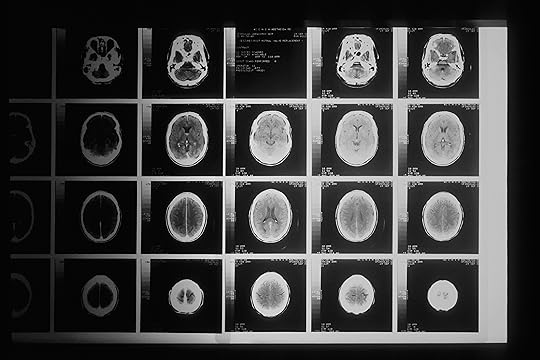

Biomedical Image Segmentation

Image segmentation is the process of partitioning a certain image into several regions of interest (ROI). In the Biomedical field segmented images can be used for anomaly detection, diagnosing diseases, computer-integrated surgery, treatment planning, studying anatomical structures, and much more. One of the advantages of having automated image segmentation methods is it’s not expensive and requires less work compared to manual segmentation. Automated image segmentation, when built ...